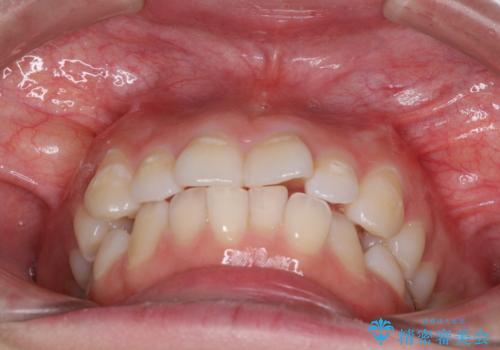

- 前歯のデコボコを気にして来院された患者様です。

当初は口元の突出感はあまり気にされていない様子だったので、インビザラインによる非抜歯矯正をお勧めしたが、ふっくらとした口元を改善したいとのことで、積極的に口元の突出感を改善することとしました。

上下左右第一小臼歯4本の抜歯を行い、ワイヤー装置による矯正治療を行うこととしました。